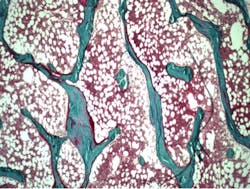

Bone samples were investigated using bone histomorphometry, a microscopic method that provides information about bone metabolism and remodeling. In children with vertebral fractures, there were changes in bone composition, such as lower carbonate-to-phosphate-ratio and increased collagen maturity (determined using FTIR spectroscopy), which could explain the increased fracture risk. The results also suggest that in children who have undergone kidney, liver, or heart transplantation, the various changes related to bone microarchitecture and turnover may be more important predictors of fracture risk than lowered bone mineral density alone. Early detection of such changes in bone quality could help prevent fractures.